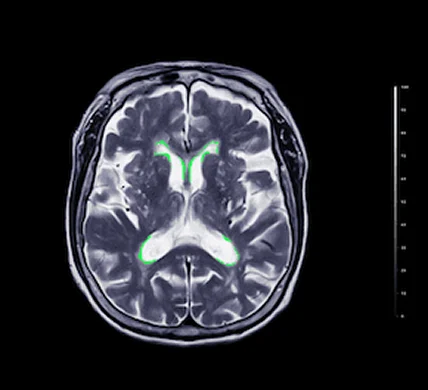

Deep learning medical imaging refers to the application of neural networks, especially convolutional neural networks, to analyze and interpret medical images. This involves training models to identify patterns in images such as X-rays, MRIs, CT scans, and ultrasounds, facilitating faster and often more accurate diagnoses.

Unlike traditional image processing, deep learning can self-learn features from large datasets, making it exceptionally effective for complex imaging tasks. With the growing availability of digitized medical data, the use of AI in medical imaging is not just valuable—it’s essential.

Deep learning algorithms can automatically detect anomalies in chest X-rays, brain MRIs, and bone fractures, significantly reducing radiologist workload.